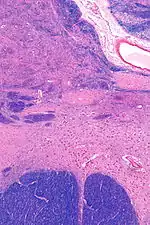

![]() Intermediate magnification micrograph of the nucleus basalis. LFB-HE stain. | |